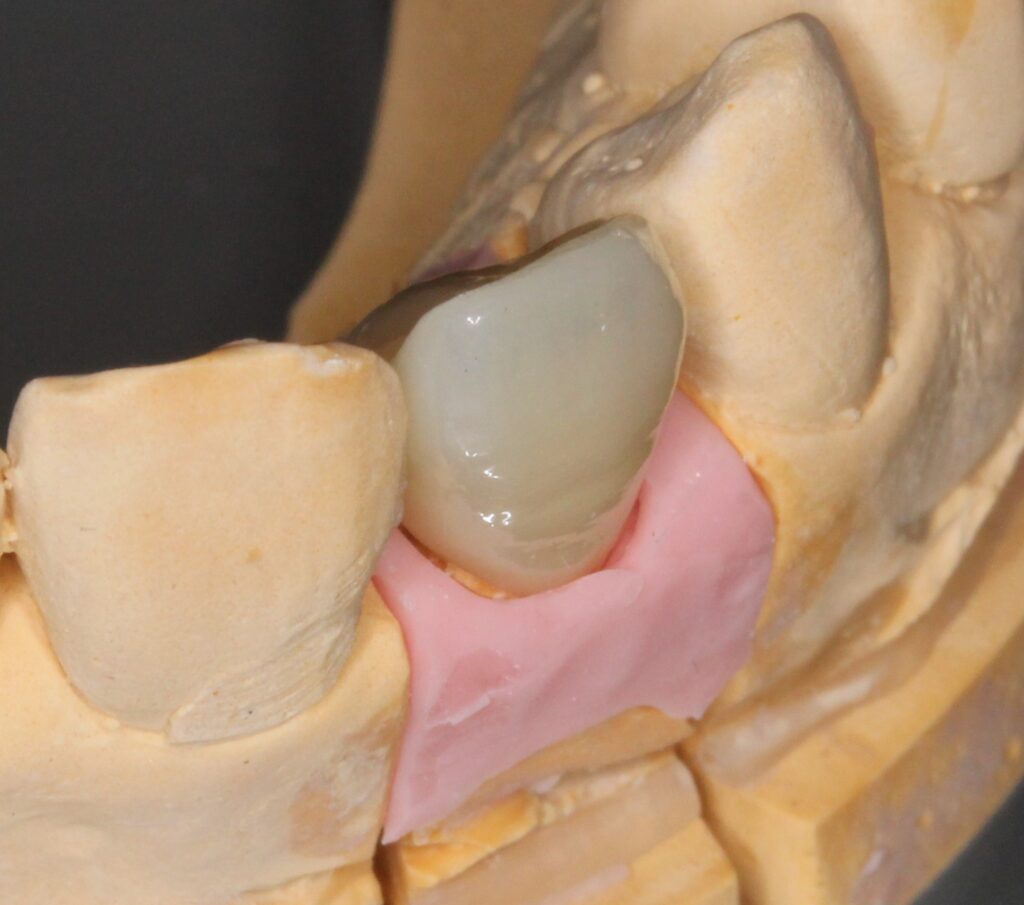

周囲歯牙形態、色調にバッチリと合わせられないと、被せ物の部分だけ目立ち造り物感がでてしまいます。

また、周囲歯肉の操作も同時に行う必要があります。

歯と歯のつけねの間の隙間(ブラックトライアングル)ができないような歯肉の取り扱いや、

被せ物と歯牙の移行部(マージン)が、歯肉内に1~1.5mm程の所にくるように設定いたします。

口腔内写真を撮影し、周囲歯牙との形態的なバランス、色調を完璧に合わせます。

これらの条件がすべて整うと、とても綺麗な見た目が再現できます。